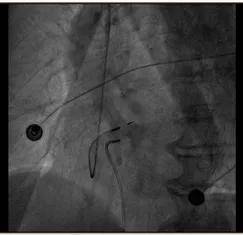

术中应用临时起搏器做保障 , 以避免发生心跳骤停 , 这是我院首例临时起搏器+希氏束起搏手术顺利实施 。

起搏器手术过程中的影像资料